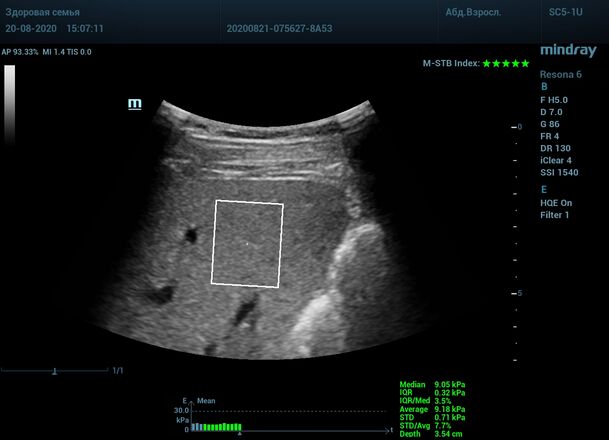

Как работает эластография сдвиговой волны? Датчик посылает плотный пучок ультразвуковых волн в ткани, ткани сжимаются, а затем возвращаются в исходное состояние за счет своей эластичности. Расправление ткани создают поперечные ультразвуковые волны, которые регистрируются трансдьюссером. Прибор во время исследования непрерывно отображает график значений плотности печени (kPa) в исследуемой зоне, достоверным считается график в виде прямой линии. Такая линия формируется путем получения близких по значению показателей. Количественным показателем является отношение межквартального интервала к медиане (IQR/Med). Допустимым считается результат с IQR/Med менее 30%. Чем данный показатель меньше, тем более точным является исследование. Для достоверного исследования в идеале нужно 10 значений.

3. - Неподвижная печень. Достигается путем задержки дыхания на выдохе. Выдох позволяет уменьшить давление на печень органами грудной клетки и брюшной полости. Задержка дыхания останавливает её. Критерием качества является индекс M-STB, выраженным в количестве звезд. Прибор определяет его автоматически. 4-5 звезд индекса свидетельствует о неподвижной печени.

Для таких сложных случаев в приборах Mindray Resona предусмотрен режим HQ Elasto. В отличии от стандартной работы эластографии HQ Elasto позволяет собрать отдельное короткое измерение в сборный график. Достаточно задержки дыхания всего в пару секунд, показатель будет записан и добавлен в график измерений. Таким образом, короткими «залпами» ультразвуковых волн по печени доктор без проблем соберет все необходимые 10 значений и проведет автоматический анализ с расчетом медианы и IQR/Med.

Приводим видео пример: использованы 3 точки доступа печени, каждое значение графика получено прицельным выстрелом HQ Elasto и собрано в единый тренд. В результате анализа 10 значений получен удивительно точный результат - статистический разброс  3.5 % IQR/Med.